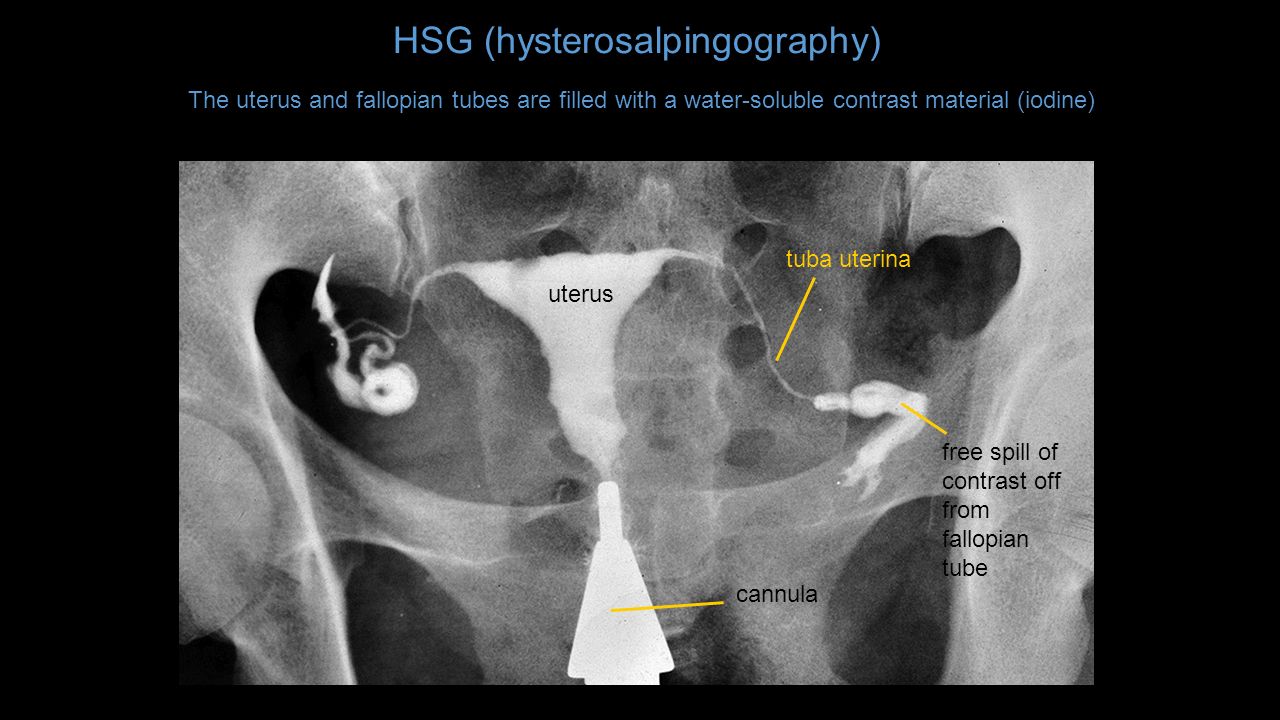

Медицинские снимки: Проходимость маточных труб

Раздел: Кадры-подсказки